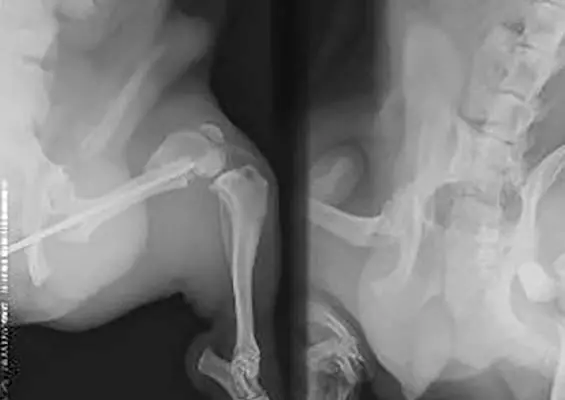

– Punktem wyjścia do stworzenia wydruku 3D jest obrazowanie trójwymiarowe. Może to być tomografia komputerowa lub badanie rezonansem magnetycznym. W przypadku przygotowywania wydruku tkanki kostnej doskonale sprawdza się tomografia komputerowa, która przy zastosowaniu kontrastu w badaniu umożliwia również uzyskanie modeli naczyń krwionośnych. Natomiast modele tkanek miękkich uzyskiwane są na podstawie wyników rezonansu magnetycznego. Jednak badanie rezonansem magnetycznym, które umożliwi dobrą obróbkę i przygotowanie modelu 3D, jest w Polsce niedostępne. Polscy lekarze wykorzystują na ogół rezonanse niskopolowe, które nie nadają się do obrazowania trójwymiarowego na potrzeby druku – wyjaśnia ekspert. – Zatem w 99% przypadków wykorzystuje się obrazowanie na podstawie tomografii komputerowej.

Badanie tomograficzne powinno być odpowiednio wykonane, bo od tego będzie zależała jakość wydruku.

– Im mniejsze odstępy między kolejnymi projekcjami, tym większa dokładność modelu. Ponadto, im bardziej obrazowany obszar jest prostopadły do wiązki promieni rentgenowskich, tym jakość obrazu będzie lepsza. Wpływ na finalny wydruk ma samo ustawienie aparatu, sposób prowadzenia badania, ale także ułożenie pacjenta – uściśla Mateusz Pawlik.